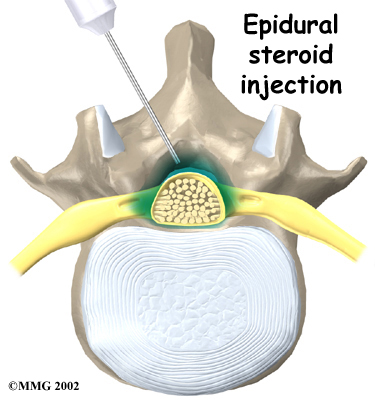

If symptoms continue to limit a person's ability to function normally, the doctor may suggest an epidural steriod injection (ESI). Steroids are powerful anti-inflammatories, meaning they help reduce pain and swelling. In an ESI, medication is injected into the space around the lumbar nerve roots. This area is called the epidural space. Some doctors inject only a steroid. Most doctors, however, combine a steroid with a long-lasting numbing medication. Generally, an ESI is given only when other treatments aren't working. But ESIs are not always successful in relieving pain. If they do work, they often only provide temporary relief.